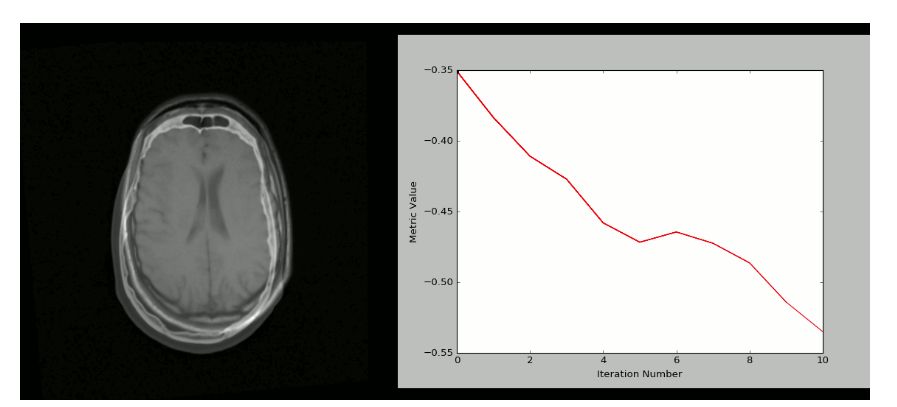

8、 SimpleITK

ITK是一个开源的跨平台系统,提供一整套用于图像分析的软件工具。

其中,SimpleITK是一个建立在ITK之上的简化层,促进其在简化原型、教育和解释语言中的应用。

SimpleITK是一个图像分析工具包,内含大量组件,支持一般滤波操作、图像分割和图形配准。

SimpleITK本身是用C++编写的,但也适用于包括Python在内的大量编程语言。

下面就是用SimpleITK和Python创建的可视化的CT/MR图: